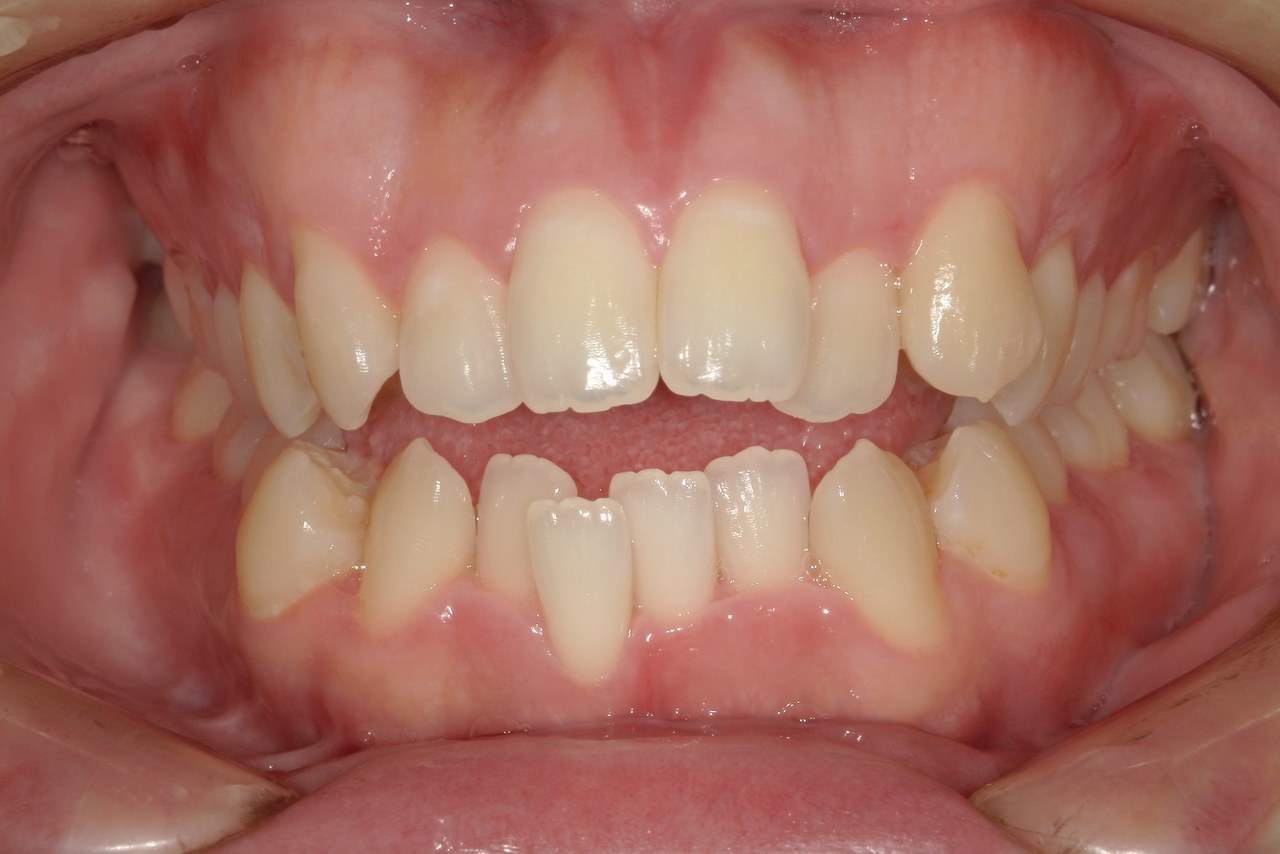

Before

浜松市中央区・自動車学校前駅のインビザラインの症例

K.M 20代女性

上の前歯が前方に出ていて横顔が気になるとの主訴でご来院。上下犬歯から犬歯までの6本が噛み合うよう、全体的に歯を内側に移動させることで、前歯の噛み合わせを整え叢生と開咬を治療しました。

​治療の期間:R5. 7/5〜R7. 1/17

​治療の価格:66万円